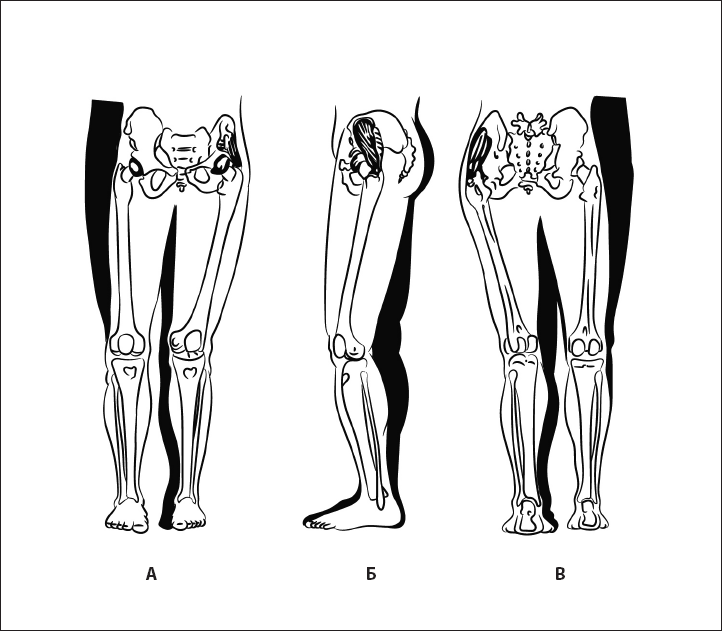

Ошибка. Смещение тазобедренного сустава наружу. При этом происходит гипотония малой и средней ягодичной мышц, а также мышцы, напрягающей широкую фасцию бедра (рис. 41).

Рис. 41. Гипотония абдукторов бедра: малой, средней ягодичной мышцы.

А – вид спереди, Б – вид сбоку, В – вид сзади.

Ошибка 1. При разгибании тазобедренного сустава крыло таза поднимается вверх. Причина – гипотоничность большой ягодичной мышцы, гипервозбудимая квадратная мышца поясницы (рис. 42).

Рис. 42. Экстензия бедра при укорочении квадратной мышцы поясницы (гипотония большой ягодичной мышцы). А – вид сзади, Б – вид сбоку.

Ошибка 2. Пациент не выполняет движение в тазобедренном суставе, а поднимает ногу за счет переразгибания в пояснично-крестцовом переходе. Причина – гипотоничная большая ягодичная мышца, укороченная пояснично-подвздошная мышца (рис. 43).

Рис. 43. Гипотония большой ягодичной мышцы. А – вид спереди, Б – вид сбоку, В – вид сзади.